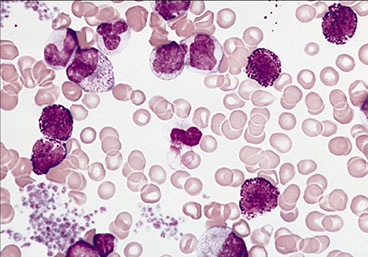

CML- chronic phase PB

Marked myeloid hyperplasia with “myelocyte bulge”.

BM Findings

- markedly hypercellular (~100% cellularity)

- markedly elevated M:E ratio

Megakaryocytic hyperplasia and clustering.

-- "Dwarf mgkcs" - lots o small hypolobated megs

Myelodysplasia is not a major feature.

Marrow fibrosis (reticulin fibrosis) is variable

Leukocytosis w myelocytes and segs. Eosinophilia common

- blasts ususally <2% on PS

- marrow hypercellular w myeloid lineage inc and dwarf megakaryocytes (small + hypolobated)

-- BM fibrosis in 30% (get reticulin stain??), which is assoc w inc megakaryo # and poor prog

-- may see Gaucher cells and sea-blue histiocytes in BM too